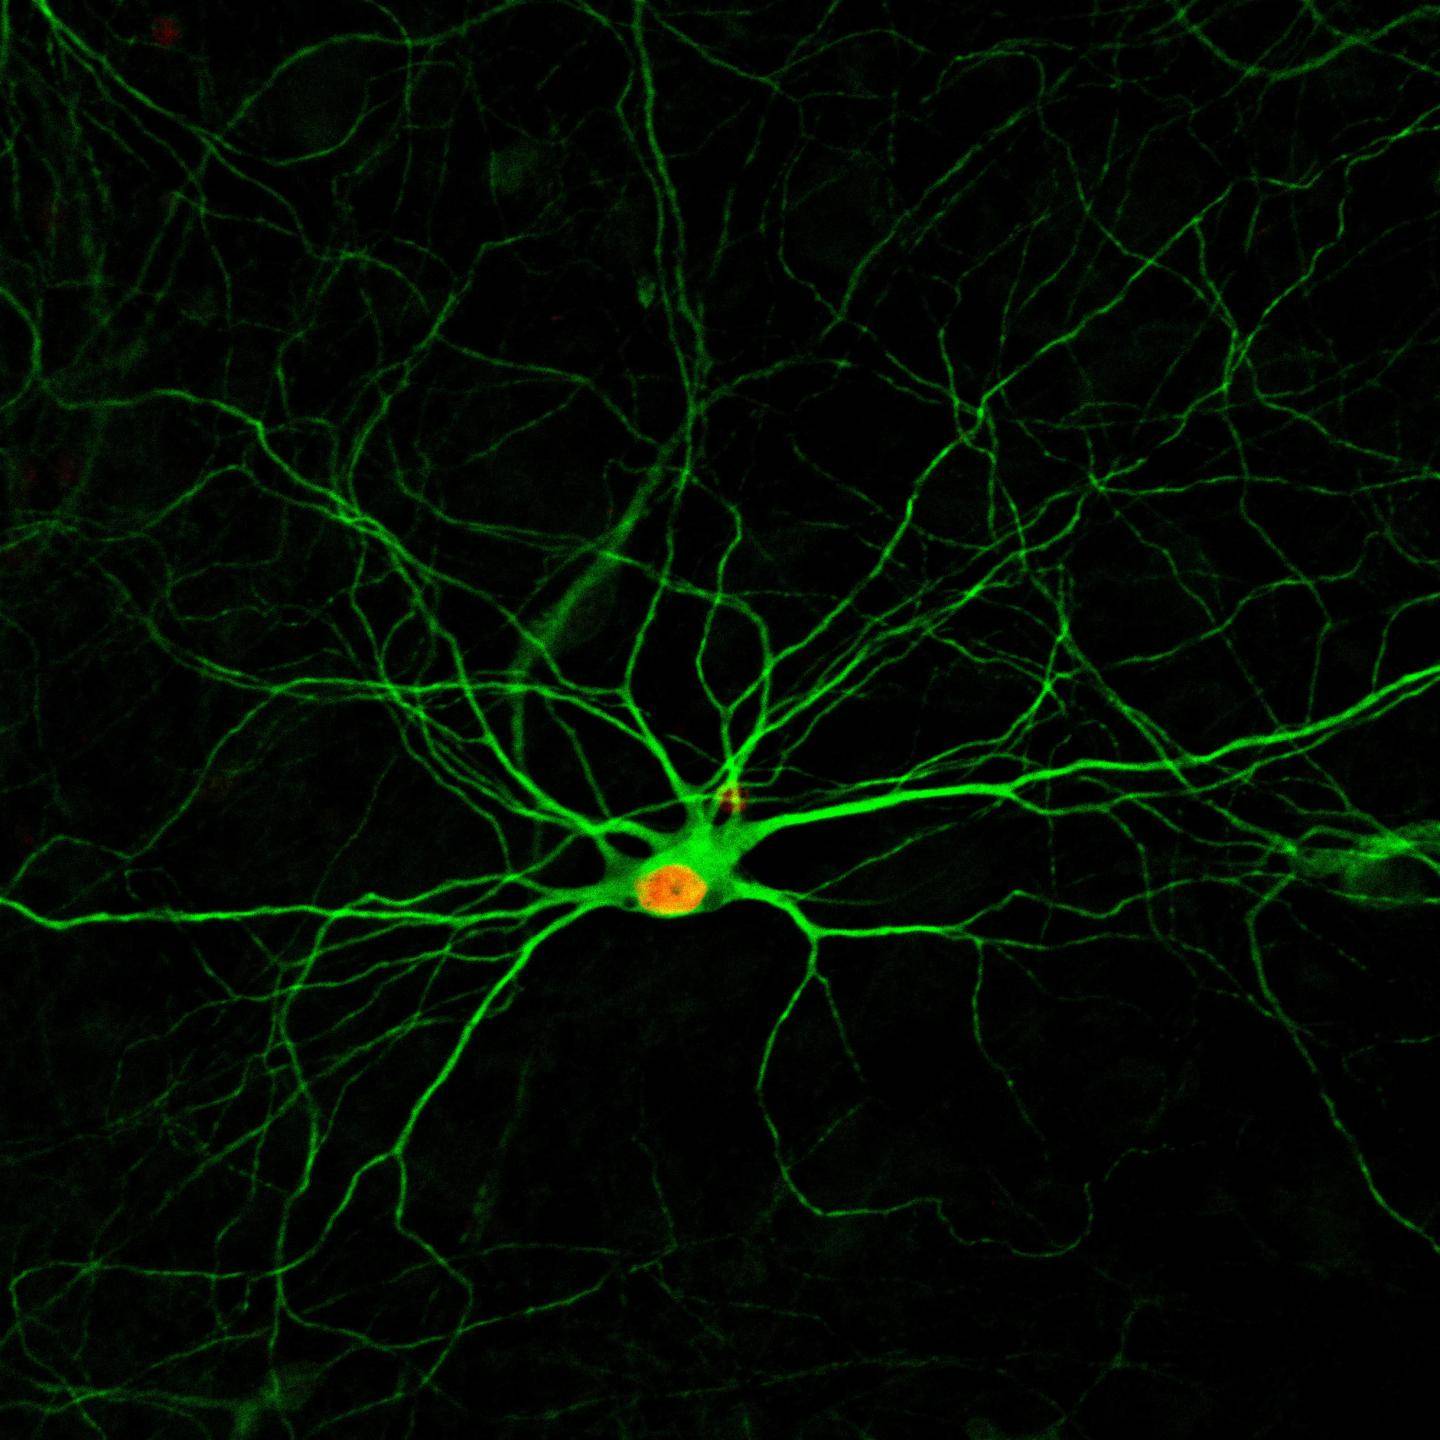

小胶质细胞(microglia)功能失调与神经退行性变密切相关,其中就包括阿尔茨海默症(AD)的发病机制,然而调控致病性小胶质细胞的基因表达的机制尚不清楚。

研究发现,绝大多数AD进展的常见风险因子,或者特异性地在小胶质细胞表达,亦或者是小胶质细胞中的表达明显高于大脑的其他细胞【1】。此外,小胶质细胞增生是许多神经疾病的一种常见组织学特征;而且由小胶质细胞和星形胶质细胞所调控的慢性神经炎症是AD的病理学特征之一。

研究也表明,转录因子CCAAT/增强子结合蛋白β(CCAAT/enhancer binding protein beta,简称c/EBPβ)调节小胶质细胞的促炎基因【2】;而且c/EBPβ的蛋白水平在AD中上调【3】。c/EBPβ调控小胶质细胞的转录程序,促进炎症和神经元细胞死亡。